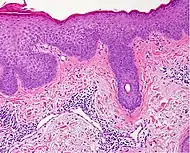

| Generally/Not otherwise specified | Typical findings, called "vacuolar interface dermatitis":[6]

![]() |